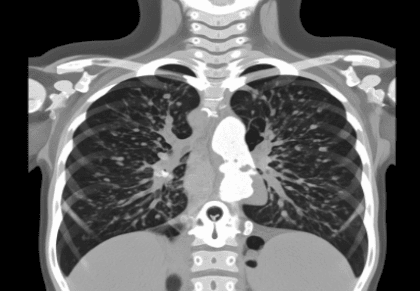

A HRCT thorax test (High-Resolution Computed Tomography) is one of the imaging methods that give doctors a direct view of the lung tissue through the clearest pictures. This advanced scan not only allows doctors to see the lung tissue in detail but also gives very clear thin slices of the lung for better and more accurate diagnosis of interstitial lung diseases, infections, and other complications through high-resolution imaging.

Many patients ask, “Why HRCT thorax test is done?” It is typically recommended when a standard HRCT chest test or X-ray does not provide enough detail to diagnose conditions such as pulmonary fibrosis, bronchiectasis, or to assess lung involvement in systemic diseases.

HRCT Thorax Test